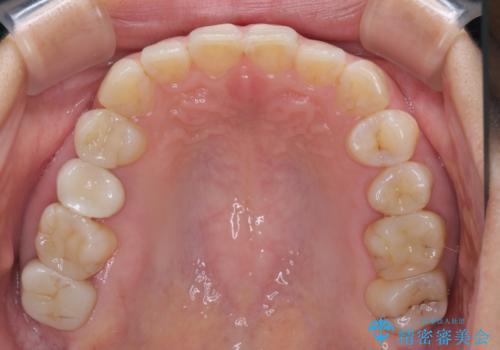

- 見た目の不揃いなセラミックと、痛みを感じる歯を気にして来院された患者様です。

右上の歯は噛んだときに何カ所か痛みを感じるとのことで、診査したところ第二小臼歯が患歯と疑われました。

患者様は他の歯にも痛みを感じるとおっしゃっていましたが、そのような所見が認められなかったため、まずは第二小臼歯を処置し、その痛みが引いた後に再診査することとしました。

痛みが引いた後、不揃いな見た目で気になっていた左下の奥歯とともにオールセラミッククラウンにて補綴治療を行うこととしました。